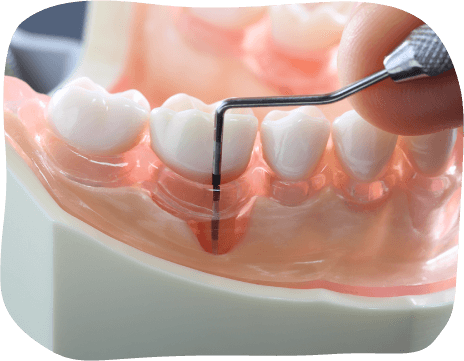

歯周ポケットの模型

歯周病は、歯と歯ぐきの境目に付着した歯垢(プラーク)が原因で、歯ぐきや歯を支える骨(歯槽骨)が壊れていく細菌感染症です。

初期の段階では痛みなどの自覚症状がほとんどなく、自分では気づきにくいのが特徴です。

そのため、知らないうちに進行し、気づいた頃にはかなり進行した状態になり、最悪の場合は抜歯に至るというケースも珍しくありません。